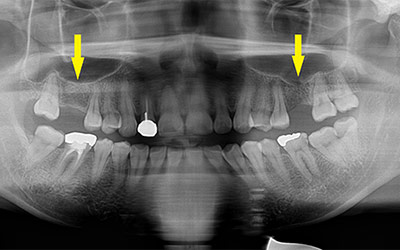

写真は初診時の患者様のレントゲン写真です。左右とも、上顎第一大臼歯を失っていました。通常のレントゲン写真では、骨量が十分かと思われましたが、CTを撮影してみると、黄色の矢印部位、左側では、少し骨の高さが足りませんでした。

CTを撮影して、測定すると、右側はギリギリ10mmぐらいの高さで、左側は6mmほどしかありませんでした。

そこで、左側はソケットリフトを併用して行いました。インプラント埋入手術後のCT、黄色の矢印部分、インプラント周囲にドーム状に補填材が白く写り、インプラントがしっかりと埋入できています。